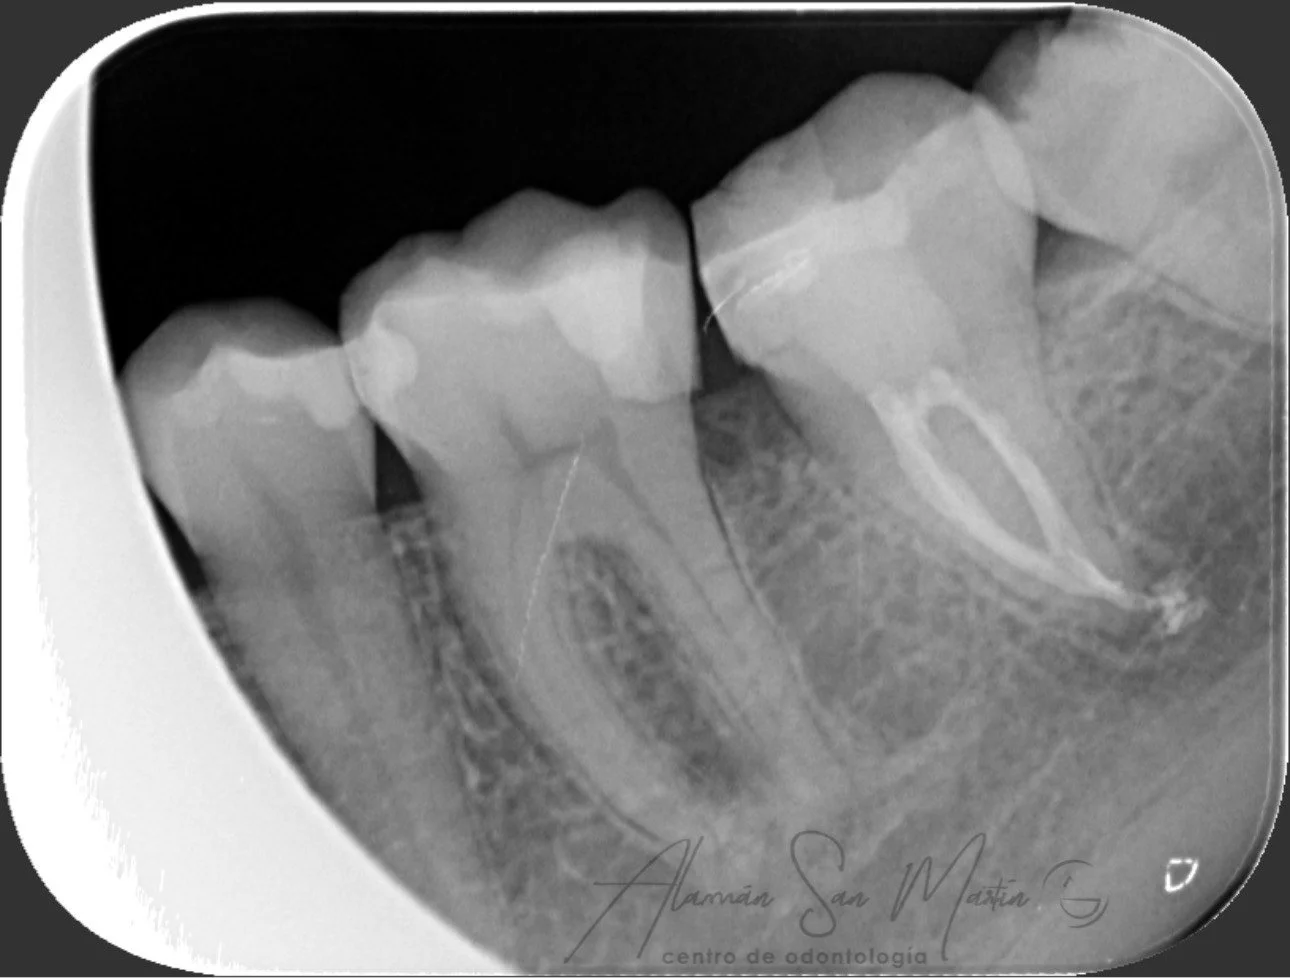

La Endodoncia consigue eliminar el nervio de los dientes con dolor por caries o algún traumatismo y rellenarlo con material biocompatible, conservando el diente sin tener que extraerlo.

En nuestra clínica se realizan endodoncias por un Especialista En Endodoncia tratando desde casos sencillos a casos complejos de retratamientos o fracasos en endodoncias antiguas.

Utilizamos técnicas avanzadas de diagnóstico en endodoncia como la Radiovisiografía Digital, el Localizador de Ápice y Técnicas Rotatorias de instrumentación de los conductos radiculares, utilizando el microscopio en los pacientes que lo requieren.